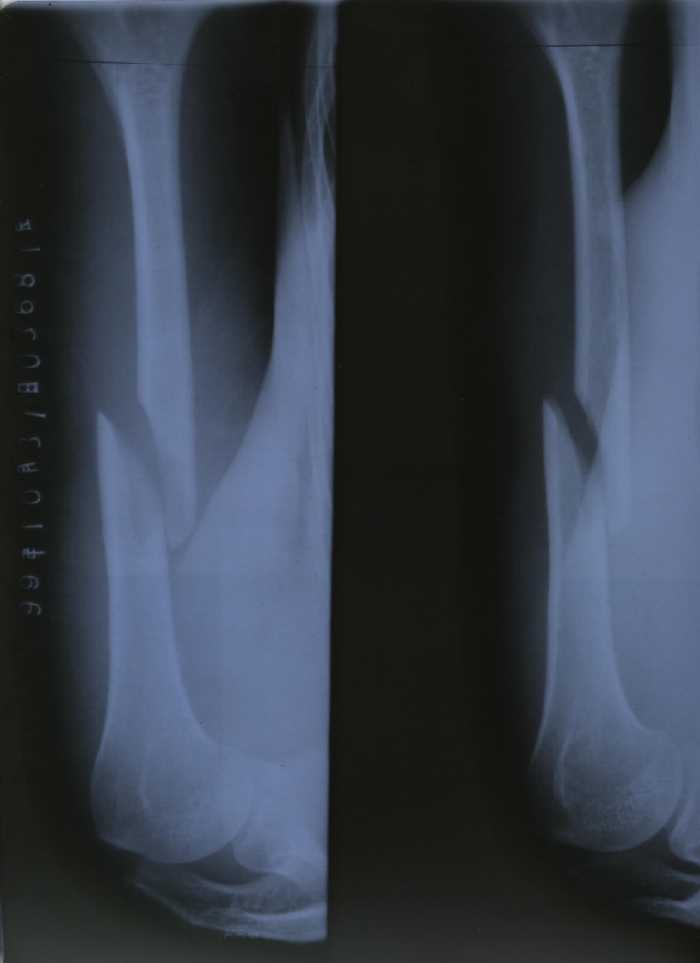

1. 项进英左臂肱骨骨折后的X光检查结果

(注:从照片和X-ray片看,这位弟子遭打的胳膊应有小血管的破裂。)

1999年10月25日,我们一行三人去天安门广场,准备上访。在广场被警察无故拦住盘问:是不是炼法轮功的。我们给予肯定的回答,就被带到附近的一个派出所,那里已经有五六十名大法弟子。登记时我们只回答自己是大法弟子。大家齐背“论语”。警察把十几人拖出,戴上手铐。(一手从肩膀下去,另一手从背后上来的那种很难受的铐法。)警察还让我们跪着,把头往墙上撞。在被铐住的情况下,一个警察还用力反复抻拉我的胳膊,听到胳臂“咔嚓”的一声,我疼得头上直冒冷汗,我知道这是自己的业力,默默忍受着。十五分钟左右,警察见我脸色不对,没有任何声响,就将我的手铐拿下,还晃晃胳膊看是不是装的,又怀疑是脱臼,装了几次但没装上。后来我们被卡车拉至北京城区的一个大院。从车上下来被审讯,然后又被送上车。审讯时一回答是大法弟子就遭毒打。我们被下车、审讯、上车两次。被脱衣服搜查后于10月26日一点左右送至看守所。检查时发现我的胳膊伤势严重。 26日早上一医生来查,当问我的名字我回答是大法弟子时,他就不看了。 27日带我去医院拍片:肱骨骨折,连医生都十分惊讶。30日上午又带我去医院拍片,几个医生会诊说要动大手术。我不愿意做手术,他们就用夹板把我的胳膊绑上,固定后再次拍片,因被强行矫正片子看似正常。警察将前后两张不同的片子均带回。当日下午又提审我, 让我回家,我被海盐公安局警察带回招待所。后找机会出去。现在全国云游。